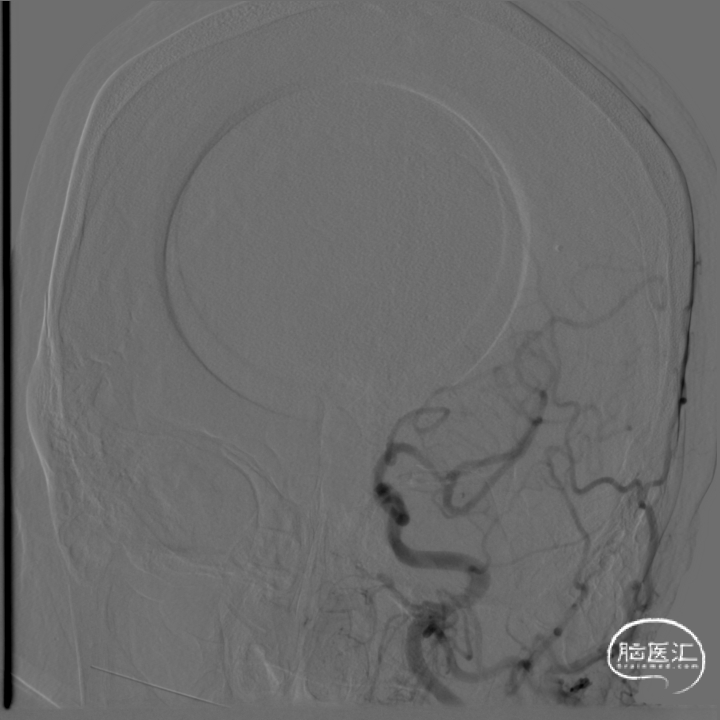

术前DSA影像:

右侧桡动脉穿刺置动脉鞘,泥鳅导丝配合6F 115cm Valent®颅内支撑导管内嵌行至右侧锁骨下动脉近右侧椎动脉起始段处,将导丝配合中间导管上行至椎动脉V3段,撤出泥鳅导丝,手推造影,显示:基底动脉中段可见重度狭窄,狭窄率约80%。